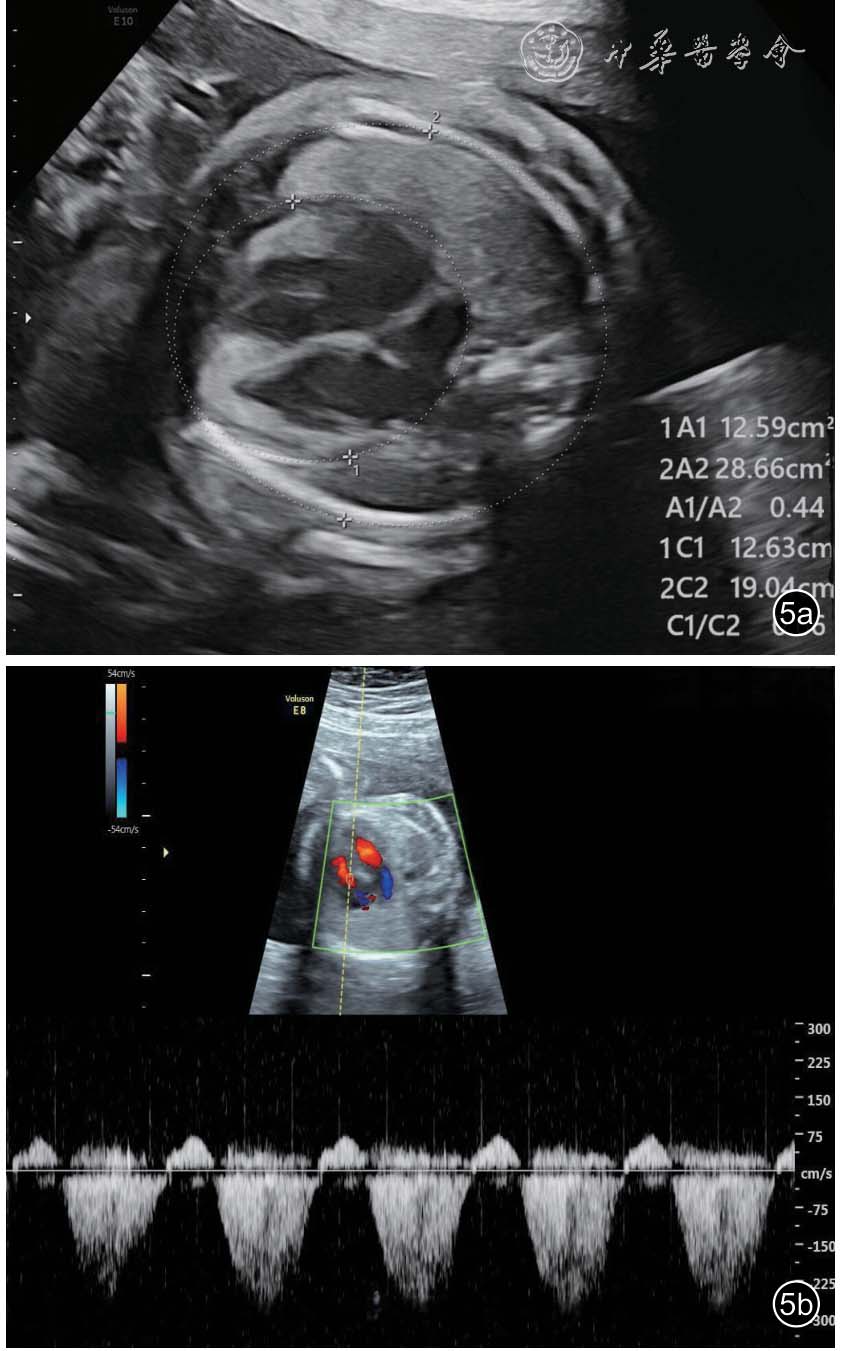

图5 双胎贫血-红细胞增多序列征胎儿孕23+5 周产前超声图像。图a:可见供血儿心胸比增大(约为0.44);图b:彩色多普勒可见二尖瓣、三尖瓣轻度反流束,连续多普勒测及反流速度约为2.7 m/s

26 例TAPS 均在中晚孕期(孕17+1~34+6 周)超声检查中发现,其中Ⅰ期11 例,Ⅱ期3 例,Ⅲ期3 例,Ⅳ期9 例,Ⅴ期0 例。共有的超声特征为:(1)供血儿MCA-PSV 增高(>1.5 MoM),受血儿MCA-PSV 降低(<1.0 MoM)( 图1);(2)“黑白”胎盘:供血儿脐带入口附近胎盘回声增强、增厚,受血儿脐带入口附近胎盘回声减低、较供血儿侧薄(图2)。其他超声特征包括:(1)24例(92%)受血儿肝呈“星空征”(图3);(2)4例(15%)供血儿肠管回声增强(图4);(3)22例(85%)心脏异常,包括心胸比增大、房室瓣反流、房室瓣频谱呈单峰、心肌增厚等征象(图5a、5b);(4)18 例(69%)多普勒血流异常,包括脐动脉、脐静脉、静脉导管A 波异常等;(5)9 例(34%)胎儿水肿,包括皮肤水肿、胸腹腔积液、心包积液;(6)15 例(57%)羊水量不均衡;(7)19 例(73%)脐带异常,包括脐带水肿、脐带插入点异常(图6);(8)15 例(57%)合并双胎选择性宫内生长受限(selective intrauterine growth restriction,sIUGR)、TTTS(表1)。对供血儿及受血儿其他超声特征进行统计分析发现,受血儿肝“星空征”、脐带水肿,供血儿肠道回声增强、胎儿水肿、心胸比增大特征比较,差异有统计学意义(P<0.05,表2)。